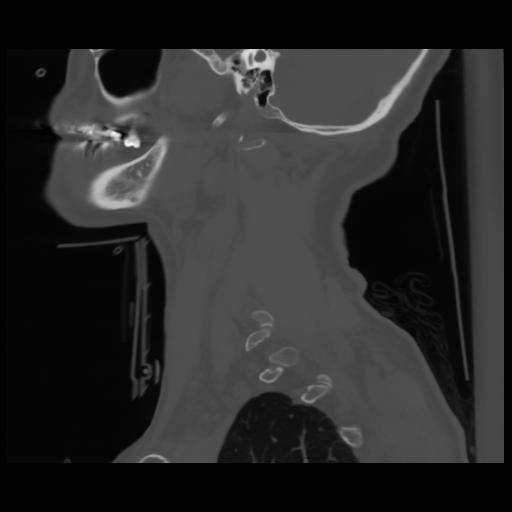

14 P.BLANDAS,,Sagittal,2.000,P.BLANDAS,Sagittal,